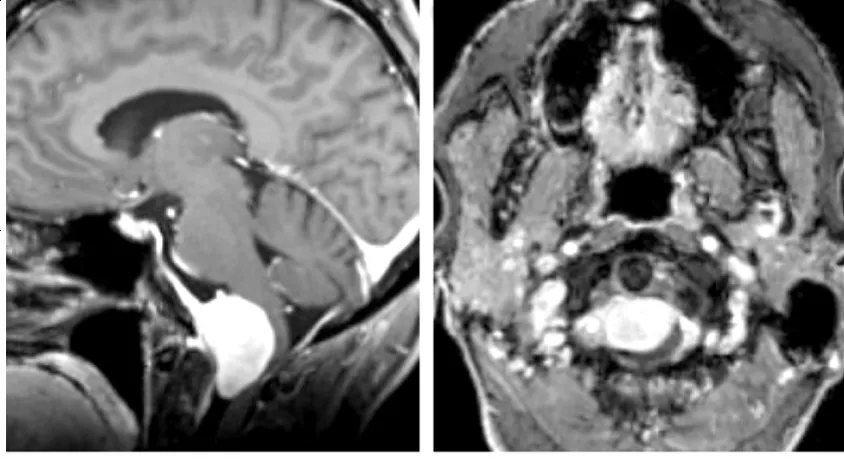

10岁时,她为战胜横纹肌肉瘤,接受了高剂量放疗。殊不知,这救命的治疗,却在脑中埋下隐患。12年前的影像(图B-C)已初现端倪,右颞叶放疗后白质损伤(圆圈)及原肿瘤区增生肉芽组织(...